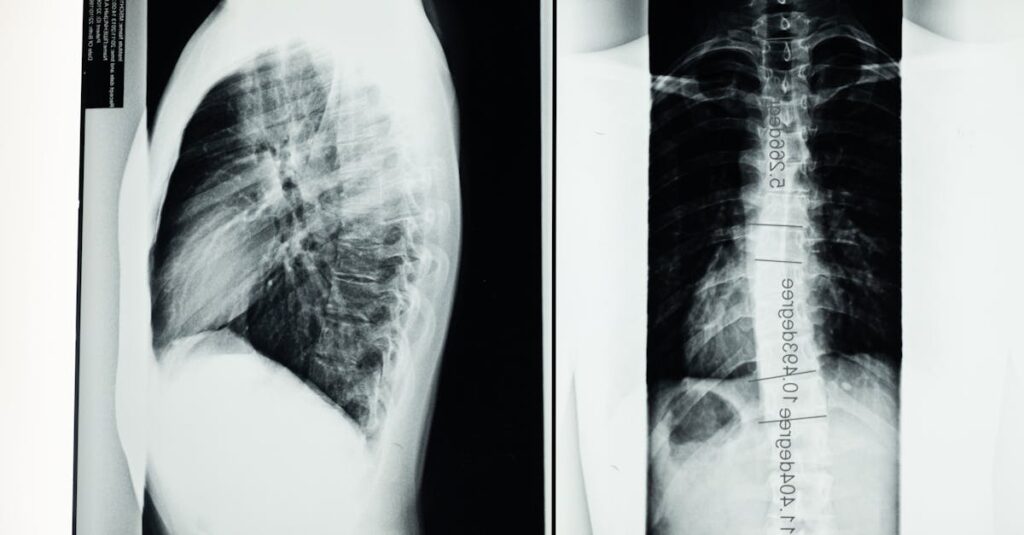

L’arthrose de la colonne vertébrale, qu’elle soit cervicale ou lombaire, est une maladie dégénérative caractérisée par une usure progressive des articulations vertébrales et des disques intervertébraux. Cette dégénérescence discale entraîne des douleurs lombaires fréquentes, une limitation des mouvements, ainsi qu’une raideur cervicale pouvant être invalidante. En particulier, l’arthrose sévère s’accompagne souvent d’un syndrome facettaire, responsable de douleurs intenses liées à l’usure des petites articulations postérieures de la colonne.

Pour mieux comprendre les mécanismes, il est utile de savoir que la dégradation des disques intervertébraux provoque une diminution de leur hauteur et leur élasticité. Cela modifie la posture et l’alignement vertébral, augmentant les contraintes sur les articulations vertébrales et accentuant le syndrome facettaire. La mobilité devient alors restreinte, et des symptômes neurologiques tels que picotements ou engourdissements peuvent apparaître.